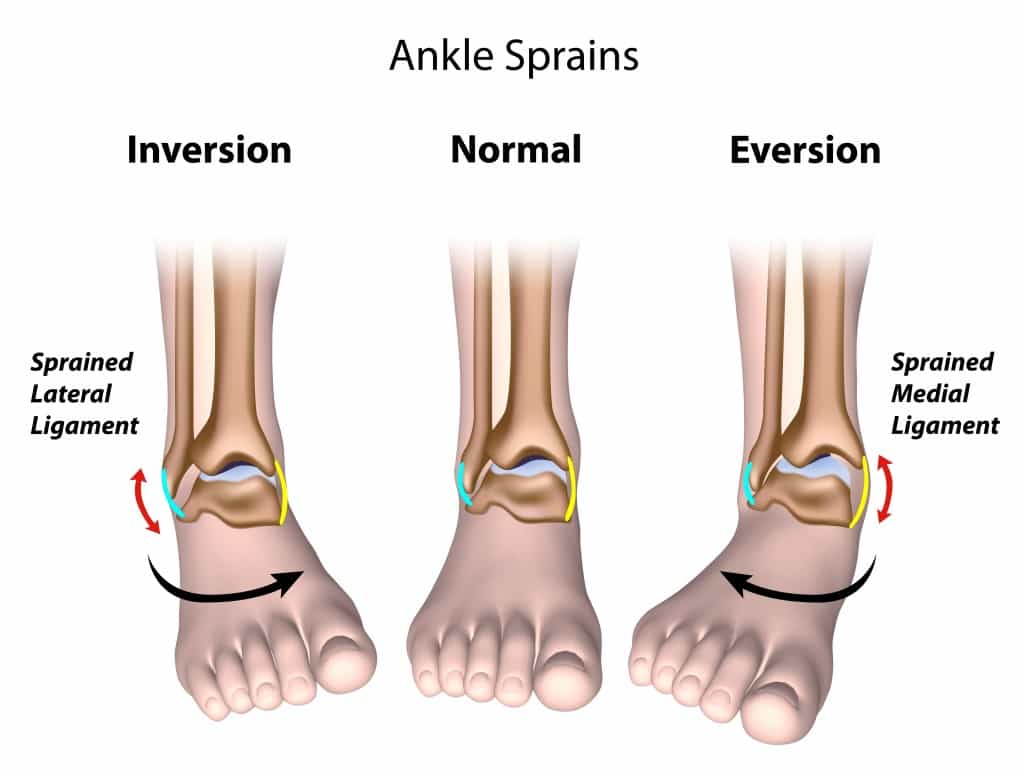

Ankle Sprain Treatment Symptoms and Prevention Dr. Mikkel Jarman